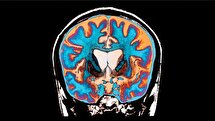

بیماری هانتینگتون یکی از سختترین بیماریهای ارثی شناختهشده است. این بیماری با علائمی چون حرکات غیرارادی و کنترلناپذیر بدن، مشکل در بلع و حرفزدن، ضعف حافظه وتمرکز، افسردگی،اضطراب، تغییرات خلقی وحتی تغییر شخصیت همراه است. با پیشرفت بیماری، تواناییهای جسمی و ذهنی بیمار بهشدت کاهش مییابد و درنهایت مرگ رخ میدهد.